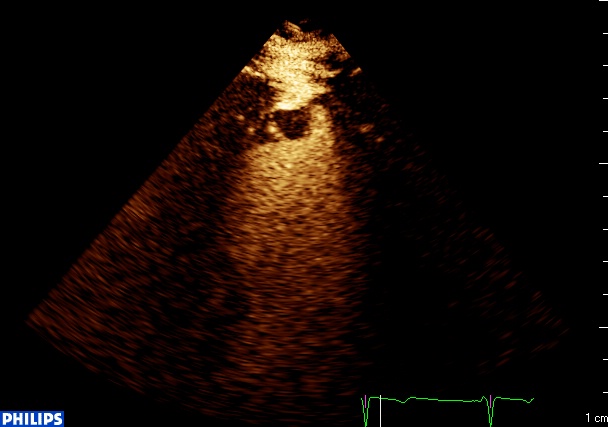

thrombus apical, echographie de contraste from fish Nip echocardiographie on Vimeo.

Et voilà le thrombus! Fini la « maison magique » (que ceux qui ont des enfants en maternelle expliquent aux autres)! Petit, rond, (comme moi), sessile, il apparait en noir, moulé par le contraste, en pleine zone akinétique.